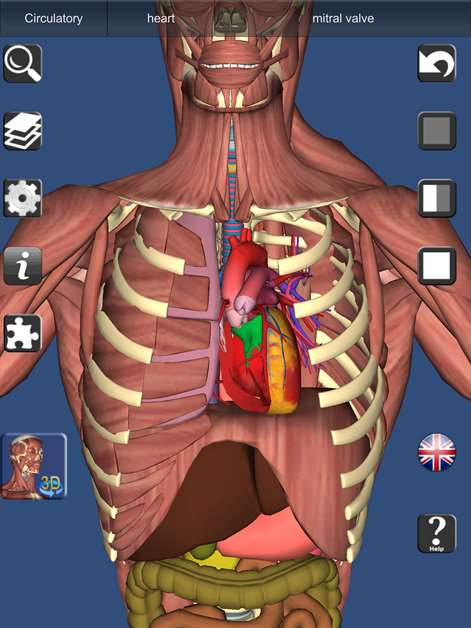

A true and totally 3D free app for learning human anatomy with position quiz, built on an advanced interactive 3D touch interface. It is completely free! (No in-app purchase). It has every bone and organ in the human body. ***From the creator of Visual Anatomy app

Features: ★ You can rotate models to any angle and zoom in and out ★ Easy to navigate and explore human body ★ Virtual dissection: Peel layers of muscles and reveal the anatomical structures below them. ★ 3D location quizzes to test your knowledge ★ Switch on/off different anatomy systems ★ Information from Wikipedia and Gray's anatomy textbook ★ Great for learning anatomy and physiology ★ It also can be used as a anatomy guide. ★ Support French, Spanish and German languages! ★ Audio pronunciation for all bone names Contents: ★ 3D Skeleton (all bones in our body) ★ 3D Ligaments (shoulder and knee ligaments only) ★ 3D Muscles (Upper body muscles) ★ 3D Respiratory system ★ Circulation (heart) ★ Nervous System (brain) ★ 3D Reproductive system (male and Female) ★ 3D Urinary system �� 3D ear